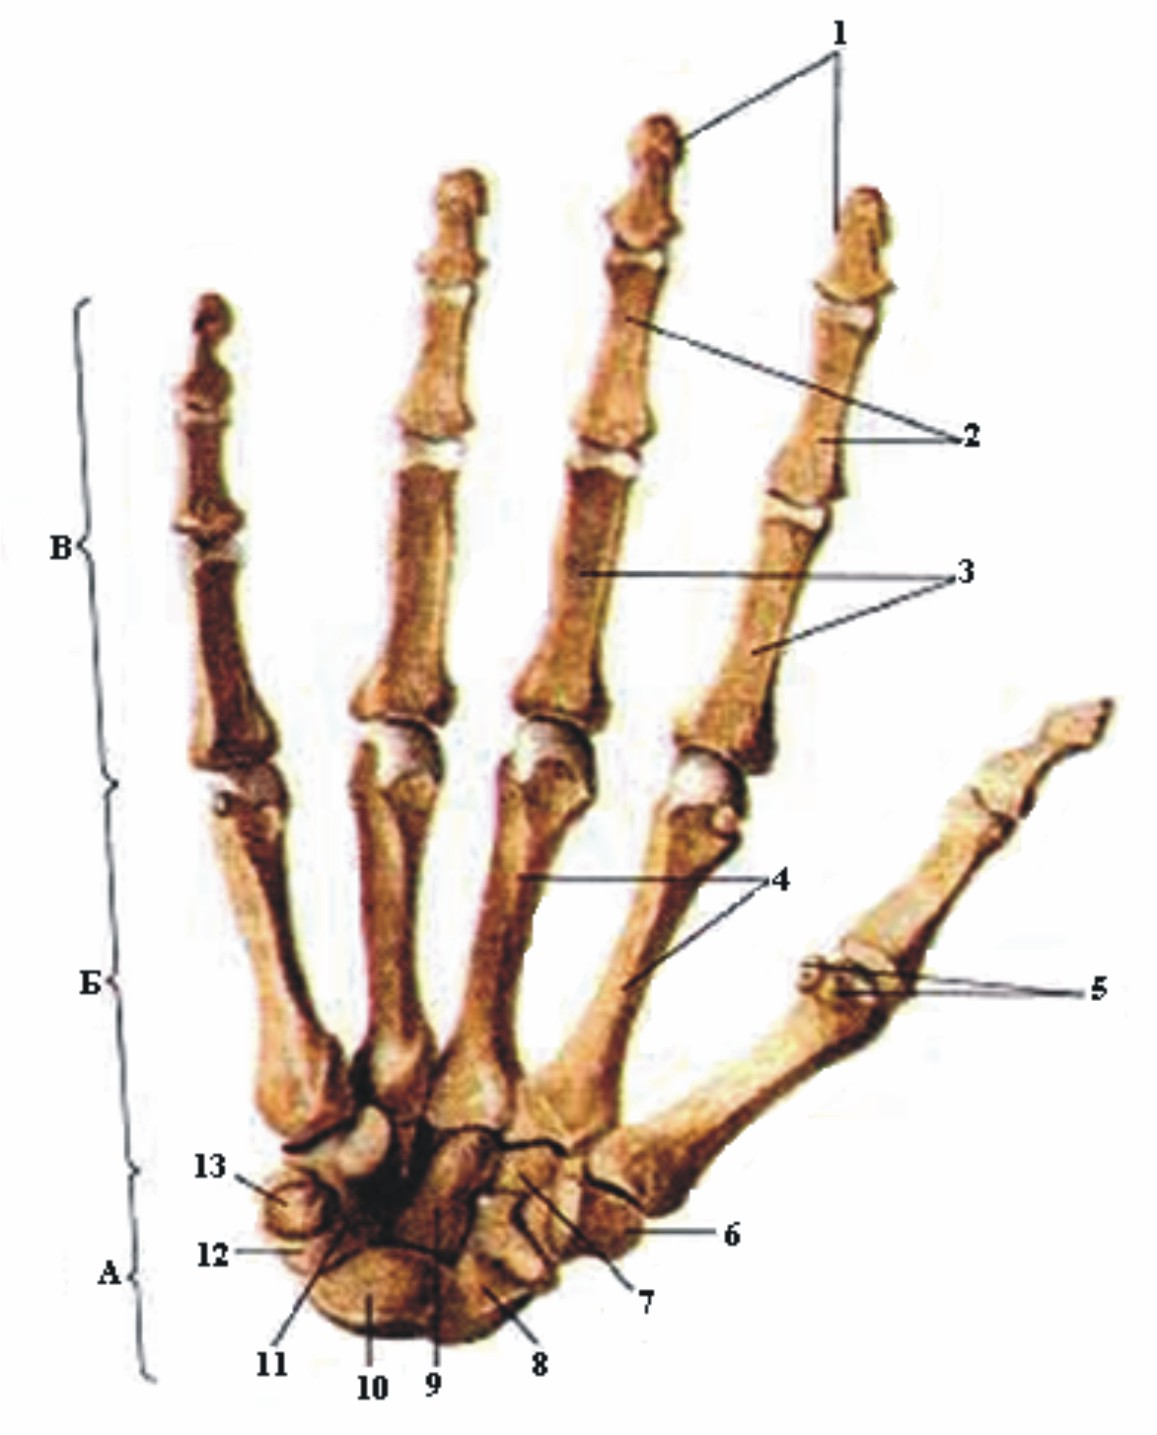

Анатомия кисти руки и строение костей